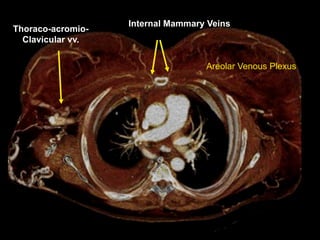

Internal Mammary Veins

Thoraco-acromio-

Clavicular vv.

Areolar Venous Plexus

Venous collaterals organized by plexus

systems – Easier, more complete to report

Cihangiroglu: J Comput Assist Tomogr, Volume 25(1).January/February 2001.1-8